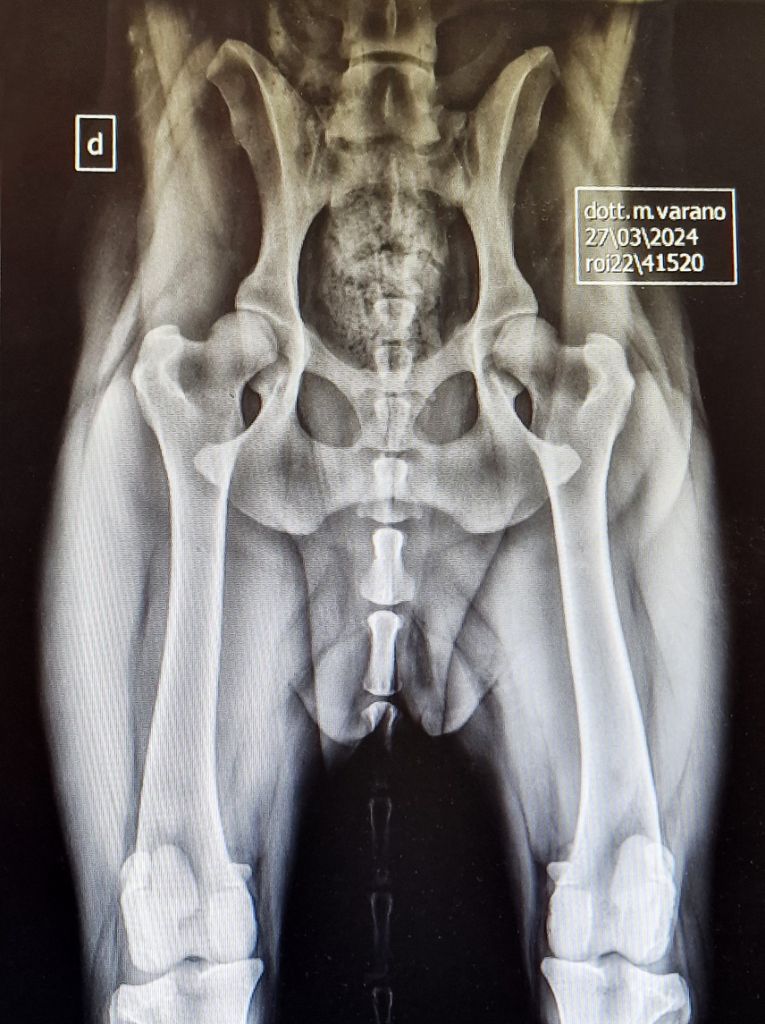

VENUS des Gardiens de Rome (Radiografie Ufficiali del 27/03/24)